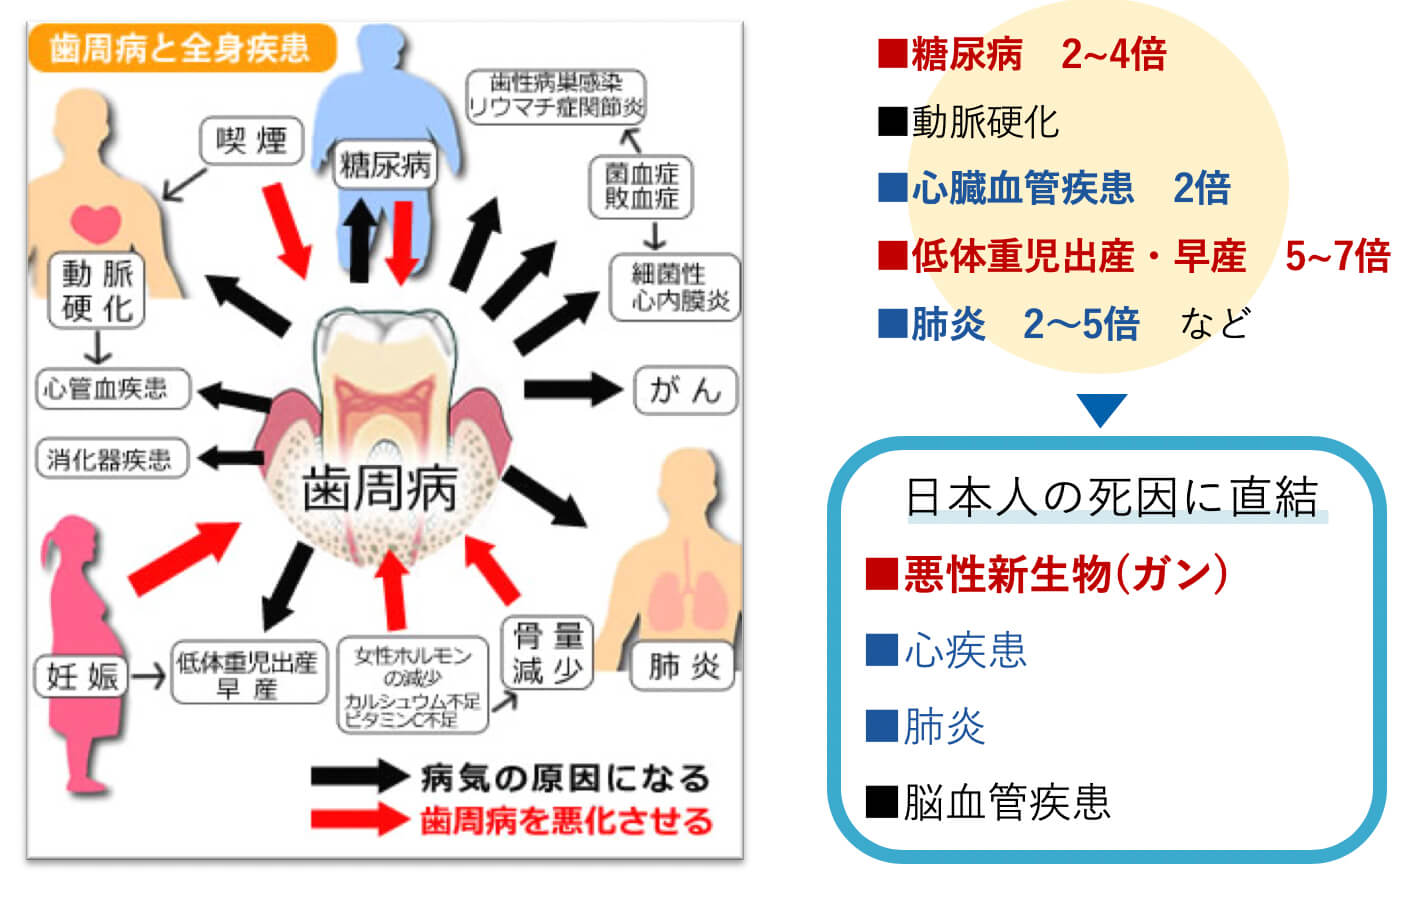

歯周病と全身の病気

お口の中の疾患がある方の全てに、これらの可能性があります。

さらに、30代以降の方の80%が、歯周病になっています。